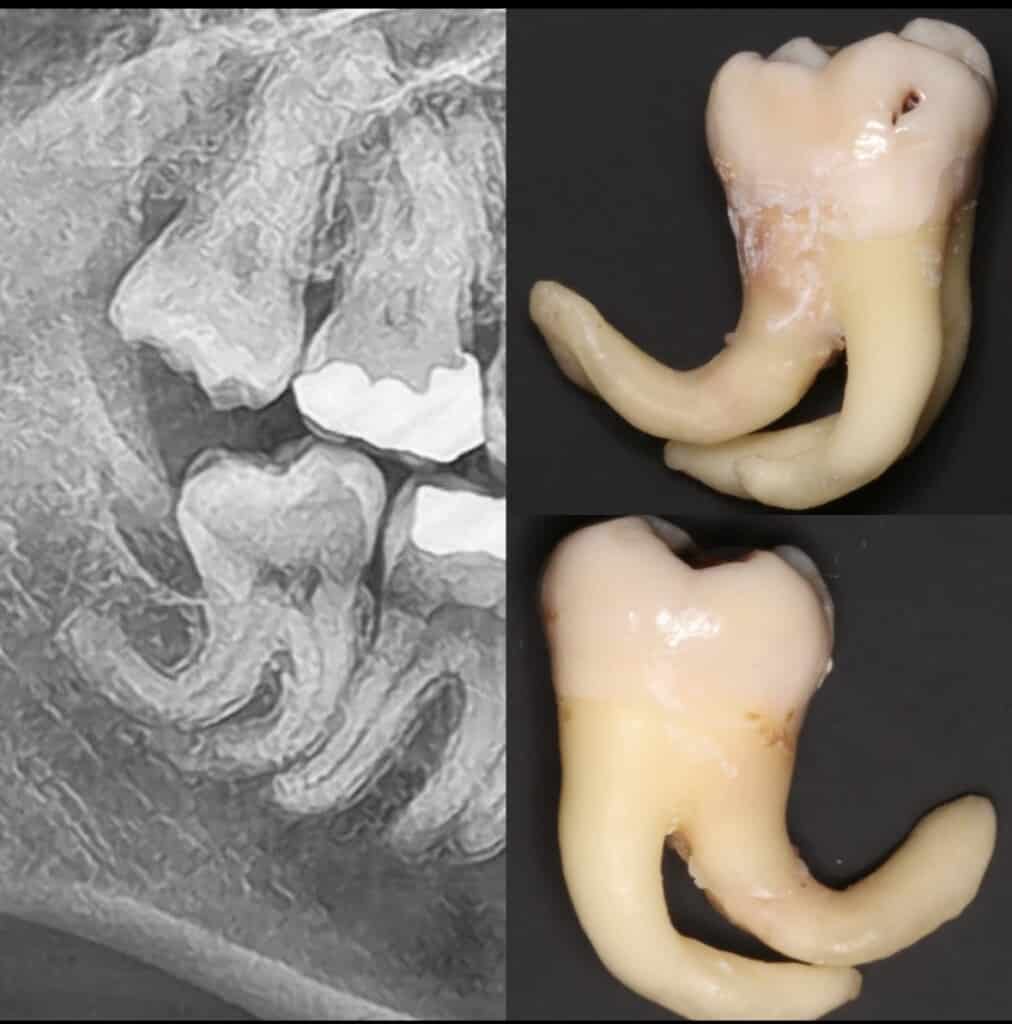

We can't get enough of amazing ORAL SURGERY! We accept referrals for complex extractions.. this one was a lovely challenge...